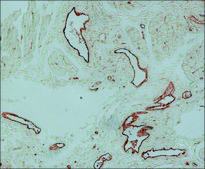

immunohistochemistry (formalin-fixed, paraffin-embedded sections): 1:1,000 using human tissue (Indirect Immunoperoxidase Labeling)

The antibody specifically reacts with the cytoplasm of human endothelial cells from normal and neoplastic blood and from lymphatic vessels. It also reacts with human endocardium, platelets and megakaryocytes. It may be used for immunohistological studies of the vascular structures in frozen tissue preparations and enzymatically pre-digested, formalin, methacarn, Bouin′s or ethanol-fixed and paraffin-embedded tissue sections.